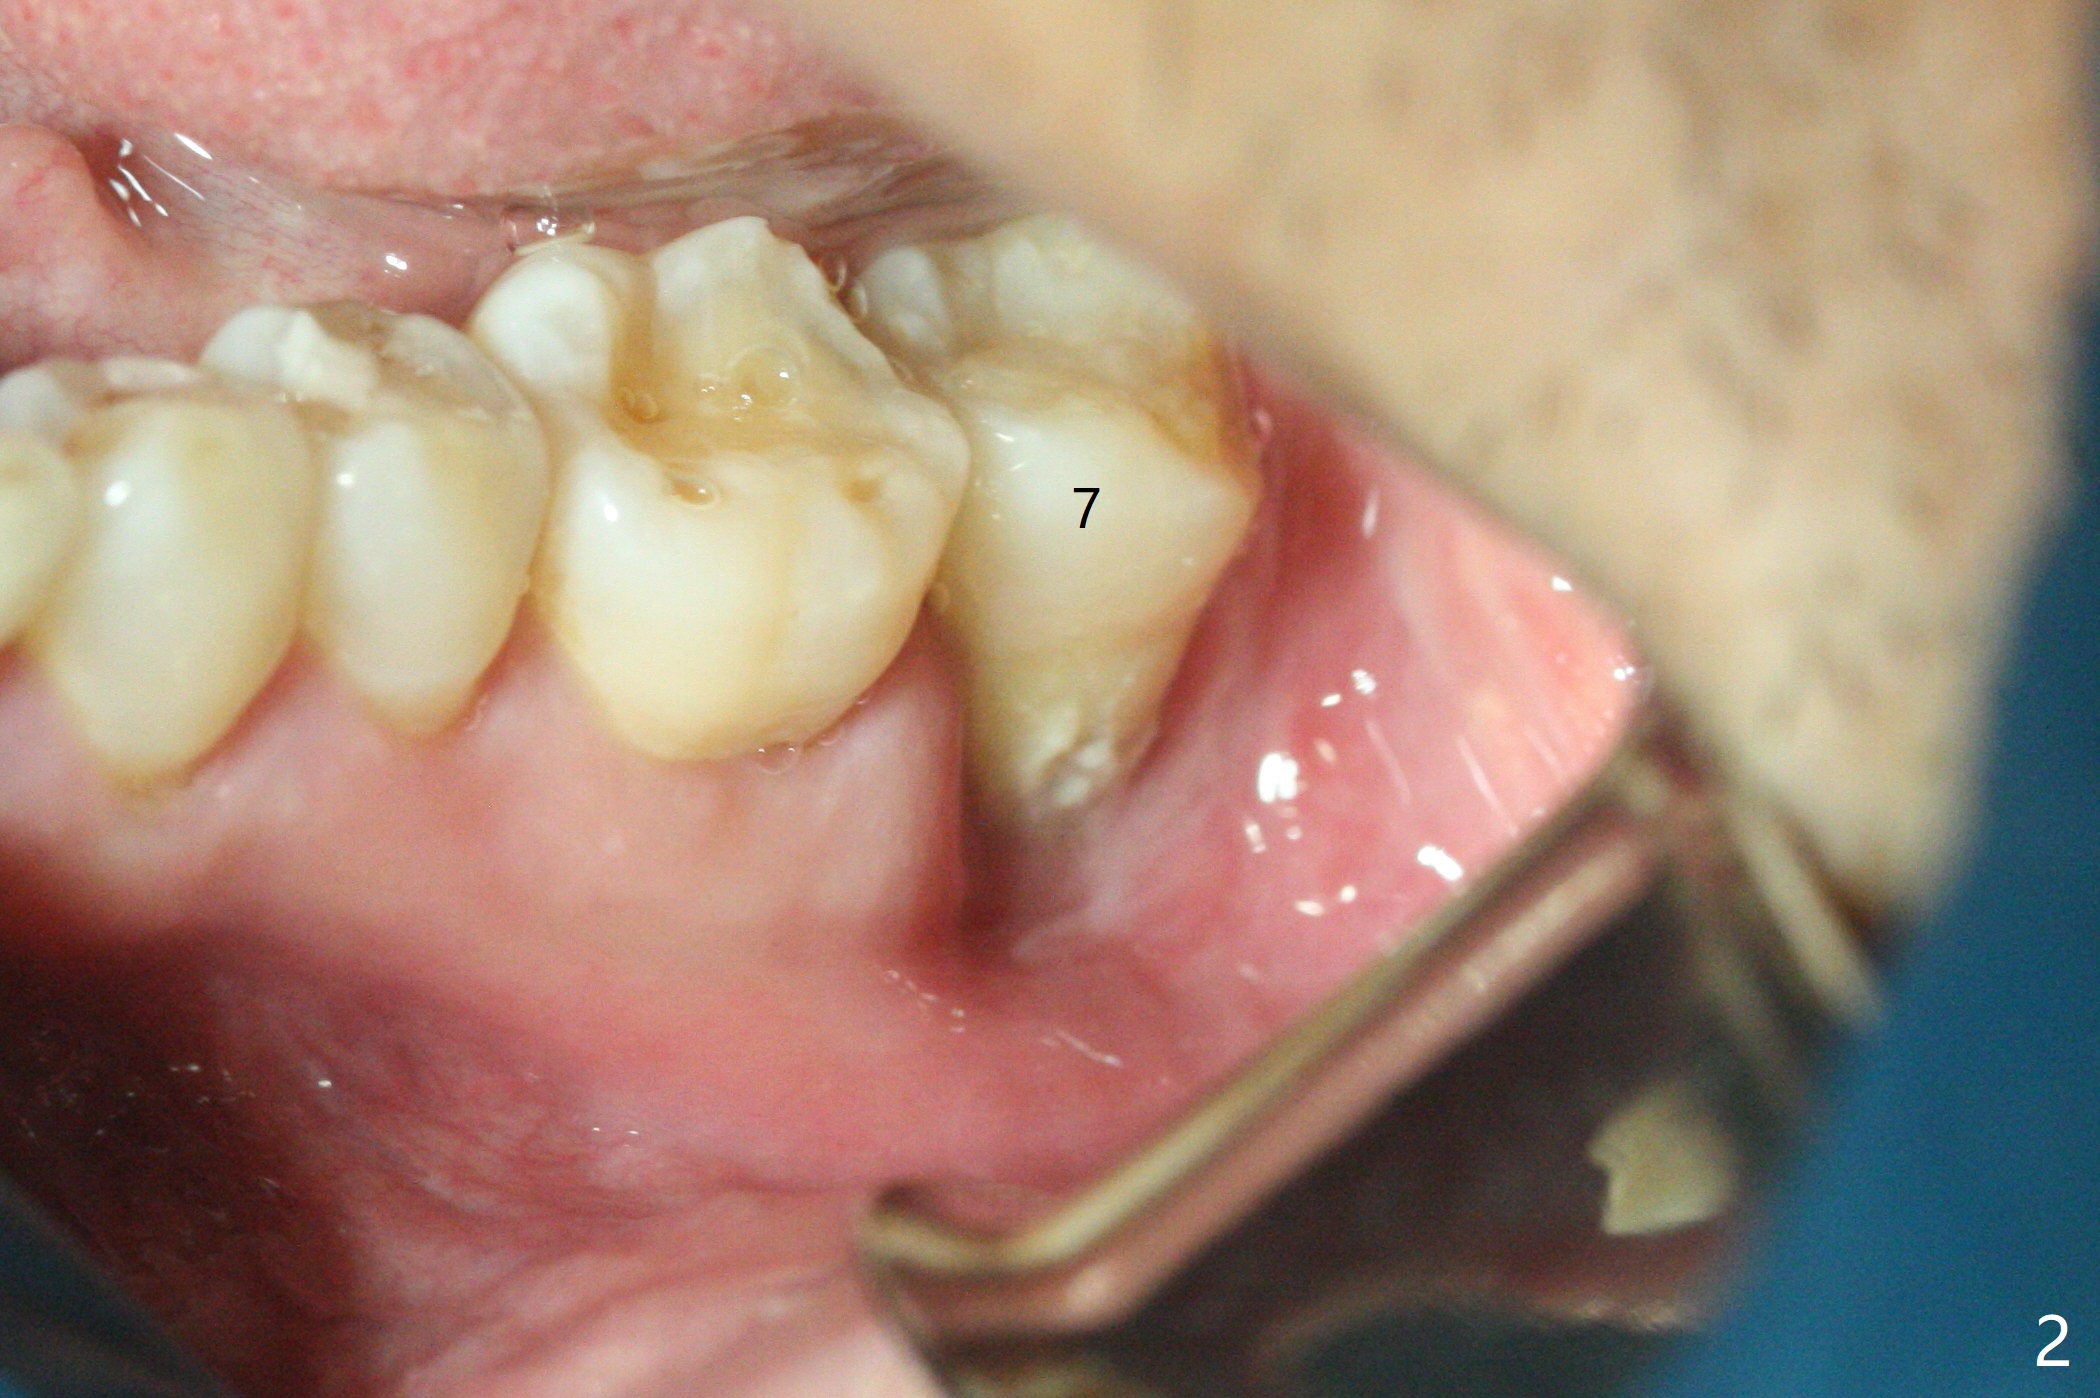

52岁男要求拔除松动左下7(图一,二),同意植骨,我们需要注意什么?我一般在类似情况下,使用浸润麻醉,但是今天改用block anesthesia,加浸润麻醉,直接将局麻药注射于牙龈,疼痛和出血控制好(图三:G(含有肾上腺素纱布)),麻醉方面有什么缺点?我不喜欢block anesthesia,万一碰到神经,麻醉深,病人不会给提醒。牙槽窝近中舌侧远中骨壁肉芽组织彻底清除;由于视野不好,切开(图四),牙槽窝底部*是软的,敢去除吗?其实我第一次向软组织投降,不敢去除,好像挺容易出血,接着敢植骨吗?其实植入粘性骨粉(皮质骨),术后CT检查表明遗留肉芽组织(图五:*),大约4毫米厚(图六),病人身体现在可忙乎了。覆盖PRF膜和不可吸收膜各一张,4-0 PTFE缝合,开口基本关闭,最后使用树脂敷料。